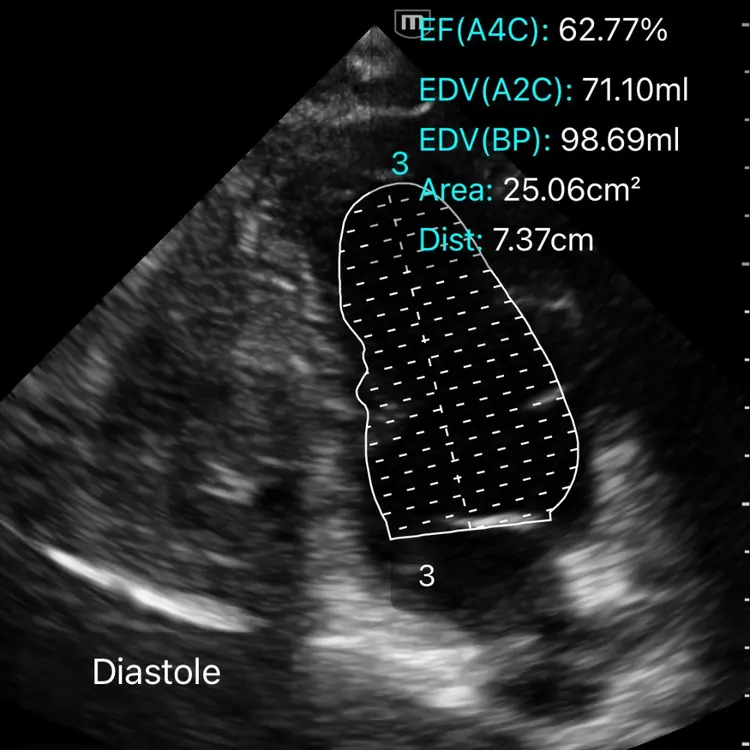

Fonction diastolique et précharge

Le remplissage, ou l’art de savoir quand s’arrêter